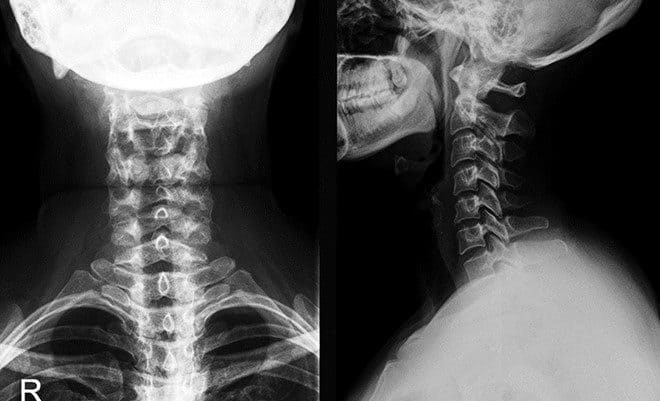

Рентген шейного отдела позвоночника

Наиболее простое и доступное диагностическое исследование, позволяющее в мельчайших деталях увидеть и оценить патологии позвоночника, локализованные в шейном отделе, – рентгенография.

Изображения, образующиеся на фотопленке или на чувствительном приемном экране рентгеновского аппарата, отражают все особенности строения позвонков, межпозвоночных хрящевых и фиброзных структур, мягких тканей.

Как правило, делают несколько снимков: в прямой и боковой проекции, для отображения межпозвоночных отверстий – в косой проекции, для изучения трех верхних позвонков – в прямой проекции с прохождением луча через открытый рот.

На полученных снимках рентгенолог-диагност в первую очередь обращает внимание на особенности костных структур. Важное значение имеет расстояние между отдельными позвонками, наличие или отсутствие деформаций тела позвонков и их отростков, позвоночного столба в целом, а также наличие трещин и переломов. Снимки дают возможность оценить плотность костной ткани, чтобы диагностировать или исключить возможность остеопороза. Мягкие ткани на рентгенограмме различимы хуже, однако изображения позволяют обнаруживать очаги воспалений, опухолевые процессы, отеки, скопления синовиальной жидкости в суставах.